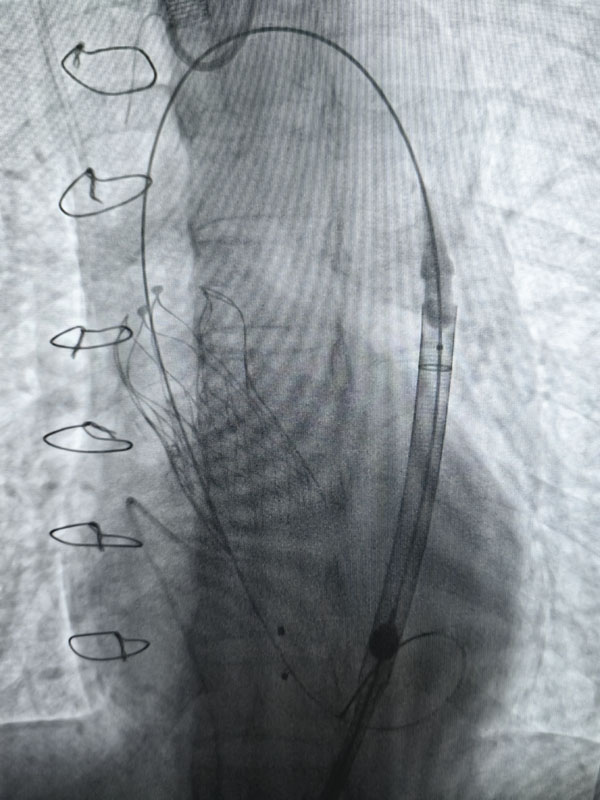

经过充分的术前准备,两台手术由心血管外科赵永波副主任主刀,赵伟超主治医师、侯五辉主治医师密切配合,选择经皮股动脉穿刺,预埋缝合器,术中反复造影,准确定位释放瓣膜,术后造影及超声提示人工瓣膜开启功能良好。为确保术中安全,体外循环小组全程保驾护航。患者生命体征平稳,术后一日均转出监护室。